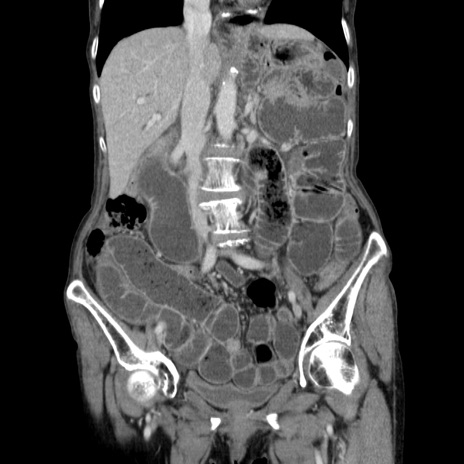

【症例】80歳代女性

【主訴】胸のつかえ感

【現病歴】約9時間前に食後から胸のつかえた感じあり、嘔吐あり、来院。

【既往歴】胃癌(全摘)、胆摘、虫垂炎

【身体所見】心窩部に圧痛あり、反跳痛なし。

【データ】WBC 5700、CRP 0.05